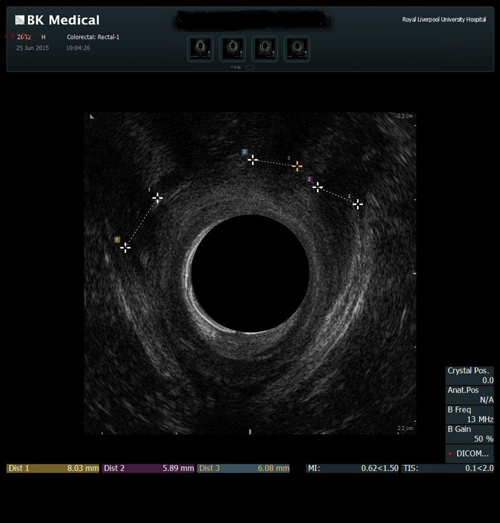

This procedure is indicated for assessment of the anal sphincter in patients with incontinence. This allows evaluation of the internal and external anal sphincters (sphincter thickness, length and scarring). It is pertinent to obtain history of obstetric trauma as well as any surgeries / intervention to aid assessment.

As with the proctogram technique, the procedure is explained in detail and consent obtained prior, and the presence of a chaperone makes the patient more comfortable. Digital rectal examination is performed as a reference to assess anal tone. Still images as well as cine of the ultrasound are taken to assess the sphincter complex (Figure 3).

Figure 3b: Abnormal / deficient low internal anal sphincter.

Figure 3c: High External anal sphincter scars due to obstetric trauma.